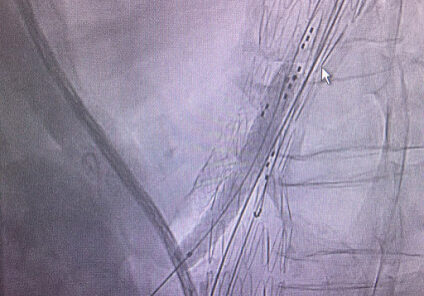

Gore Viabahn VBX Covered Stent plays important role in addressing complex aorta-iliac occlusive3

Gore Viabahn VBX Covered Stent plays important role in addressing complex aorta-iliac occlusive.

VBX as primary choice

VBX as primary choice for complex aorto-iliac reconstructions.